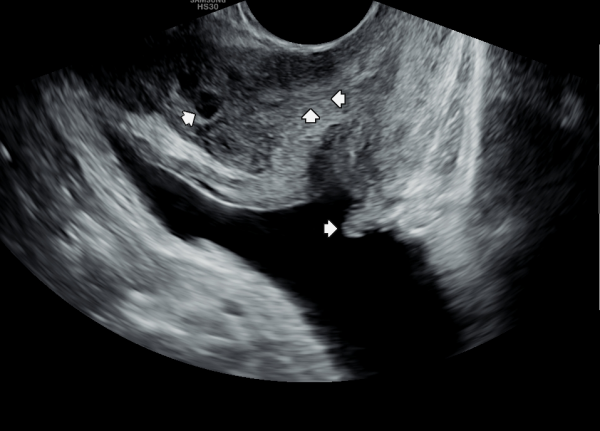

첫 내원 당일 측면 경직장 전립선 초음파 검사상 사정관 입구의 결석과 폐쇄로 사정관 낭종이 관찰되고 사정관에 탈락된 상피세포가 쌓여 사정관이 막히고 있으며 요도 협착등 배뇨 장애로 방관내 조직의 이상 증식이 관찰되는 초음파 사진 입니다.

On the first day of the visit, a lateral transrectal prostate ultrasound revealed stones and obstruction at the entrance of the ejaculatory ducts, leading to ejaculatory duct cysts. Detached epithelial cell debris was observed accumulating and blocking the ducts. In addition, abnormal tissue proliferation within the bladder was noted, likely due to urethral stricture and associated voiding dysfunction.